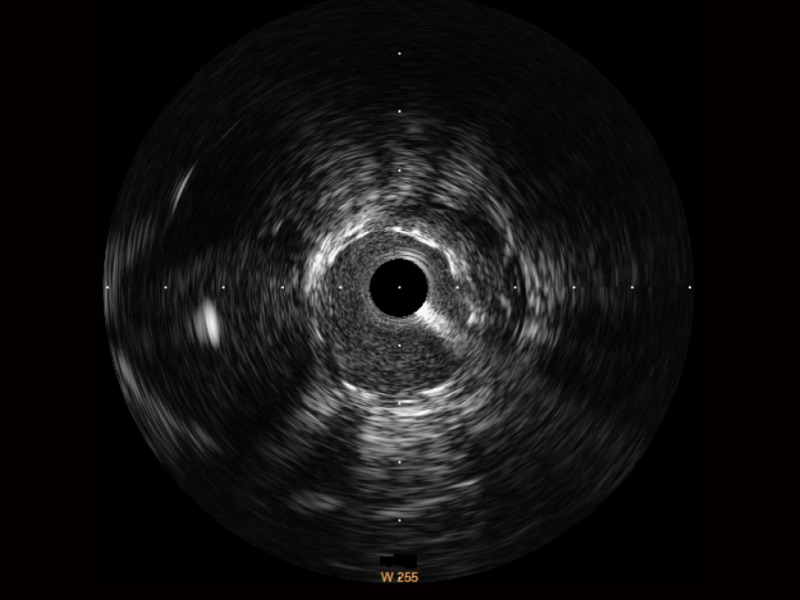

单晶超宽频IVUS VS 传统陶瓷材料IVUS

米兰官方网站超宽频成像技术覆盖20-80MHz1或20-90MHz2频率范围, 提供优异的分辨力同时也保证充足的穿透深度

对比传统IVUS导管成像,米兰官方网站宽频IVUS图像的近场支架梁显影更细腻,远场中膜外血管仍清晰可辨,兼顾远中近,兼顾分辨力与穿透深度